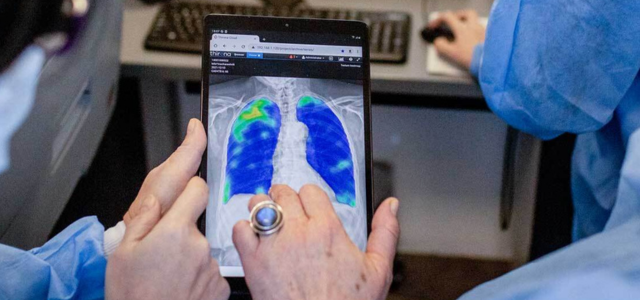

The input and output are still the same: CAD4TB processes frontal chest radiographs from any type of digital X-ray equipment and produces a heatmap, indicating with colours which parts of the lungs are likely abnormal, and a score between 0 and 100. The higher the score, the more likely that the subject on the image has tuberculosis (TB).

Figure 3. Two examples of chest radiographs of children both four years old. The left image is normal, and no abnormal regions are seen in the heatmap. The score of CAD4TB version 6 for this case is 22. The right image has clear abnormalities, accurately detected by CAD4TB 6. The image gets a score of 86.